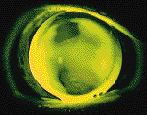

Retinoscopy and corneal topography -- Performing retinoscopy or corneal topography over soft toric lenses may provide a clearer picture of why a patient does not have sharp acuity with a soft toric that centers and moves well. In many cases, the lens does not drape the cornea smoothly, resulting in irregularities in the optic zone. This translates into unstable and blurry vision. A dark area in the center of the retinoscopy reflex indicates that a lens is too steep. An irregular corneal topography pattern in the central area also indicates poor draping (Fig. 3). In either case, flattening the base curve or using a thinner design allows the lens to drape the cornea more smoothly and usually solves the problem.

FIG. 3: Corneal topography of front surface of soft toric lens. Note

central distortion with inferior steep zone indicating poor draping characteristics of the

lens.